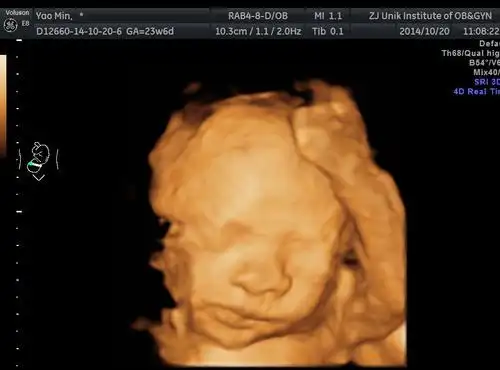

四维彩超和宝宝的长相差别大吗?这些特征存在误差,丑俊难辨

孕妇做四维彩超胎儿鼻子扁又大胎儿也是有苦说不出啊

宝宝四维照片和出生对比

四维彩超中的胎儿和生出来的胎儿会一样吗3张图告诉你